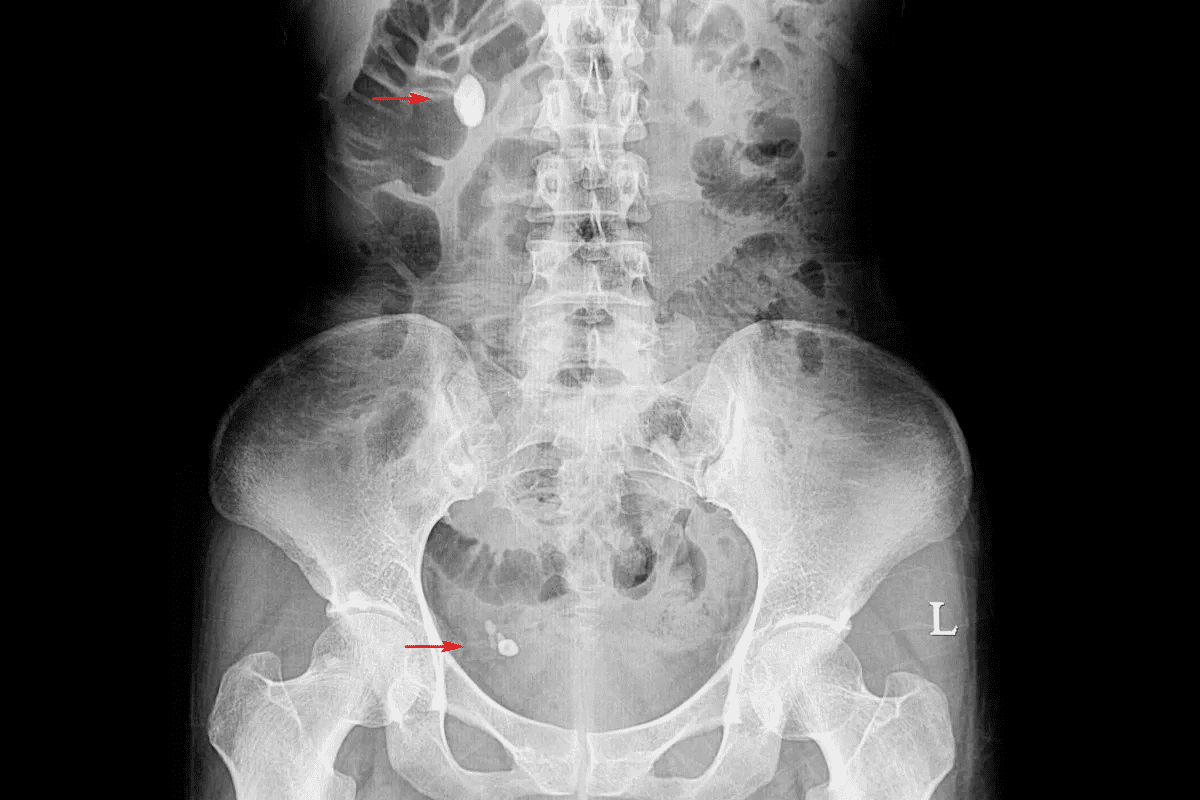

To diagnose kidney stones, doctors use a mix of imaging tests and lab tests. This method helps them find kidney stones and understand how they affect digestion.

Imaging tests are key in finding kidney stones. The main tests are:

These tests help doctors know the size, location, and number of stones. This info is key for planning treatment.

Kidney stones are diagnosed with imaging tests like CT scans, ultrasounds, and X-rays. Laboratory tests also analyze urine and blood samples.